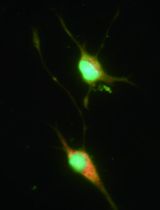

Tumors are heterogeneous microenvironments where complex interactions take place between neoplastic cells and infiltrating inflammatory cells, such as tumor-associated macrophages (TAM) and tumor-associated dendritic cells (TADC). The relevance of tumor-infiltrating mononuclear myeloid cells is underscored by clinical studies showing a correlation between their abundance and poor prognosis (Laoui et al., 2011). These cells are able to promote tumor progression via several mechanisms, including induction of angiogenesis, remodeling of the extracellular matrix, stimulation of cancer cell proliferation and metastasis and the inhibition of adaptive immunity (Laoui et al., 2011). Moreover, mononuclear myeloid cells are characterized by plasticity and versatility in response to microenvironmental signals, resulting in different activation states, as illustrated by the presence of distinct functional TAM subsets in tumors (Movahedi et al., 2010; Laoui et al., 2014). Here, we describe a valuable isolation technique for TAM and TADC permitting their molecular and functional characterization.